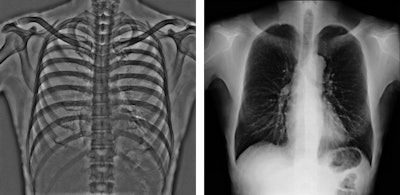

Fujifilm staff are demonstrating a range of DR panel and image processing systems designed to improve workflow and patient outcomes. The company's Virtual Grid image processing software can adapt contrast to improve image quality for exams acquired without a grid. While this processing has been available for some time for chest and abdominal examinations, it can now be used for all body parts, offering a potential workflow improvement for mobile imaging applications where the use of a physical grid is most challenging and can disrupt patient comfort.

Tests on phantoms have shown that the product offers comparable image quality at a 30% to 40% lower dose than with a physical grid, so the implications for dose reduction with this image processing technology cannot be ignored, according to a company statement.

The emphasis of Philips' researchers has been on developing technologies for improving diagnostic quality while eliminating inefficiencies when using mobile digital radiography systems at the patient's bedside. The new SkyFlow scatter correction algorithm reduces the effect of scattered radiation for nongrid bedside chest exams, allowing the operator to obtain DR images with grid-like contrast, but avoiding the time and effort involved in attaching and detaching a grid.